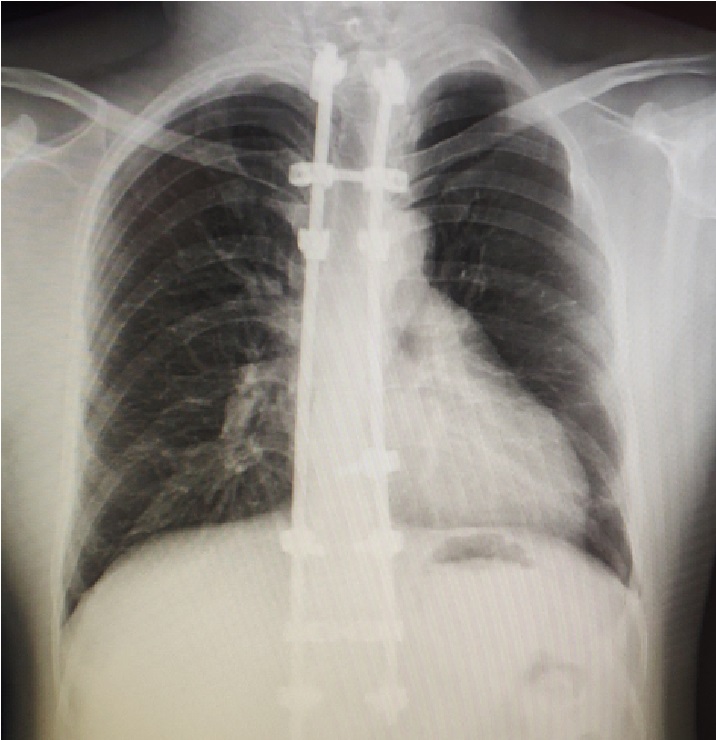

入院查体,患者左侧胸壁突起,右侧低平,呈不对称型鸡胸。背部有长约30cm长的手术疤痕。X线检查提示前胸壁双影。经充分术前准备,我们采用无管技术为患者实施了微创手术。术中使用两条钢板做塑形,手术历经30分钟完成,操作顺利,未出现并发症,术后畸形完全消失。